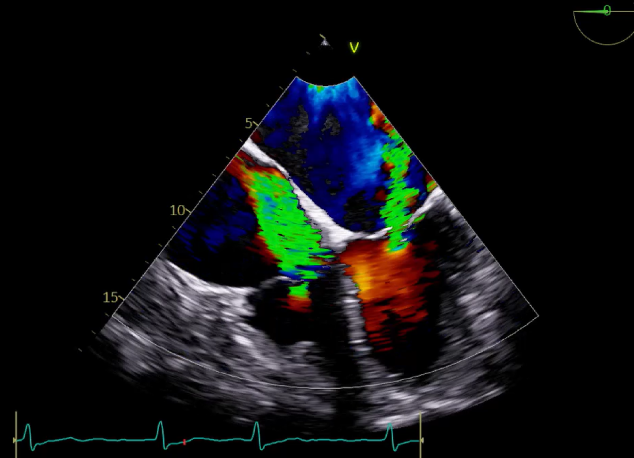

术中超声

确定房间隔穿刺点:靠后

2D视图下测量大鞘长度2cm

3D视图打开夹子

X-plane:下第夹子尝试捕获2区

X-plane:测量前叶长25mm,后叶长14.2mm

X-plane:计算前叶捕获长度8mm,后叶捕获长度7mm

3D视图下观察二尖瓣双孔形态

3D-color:残余少量返流